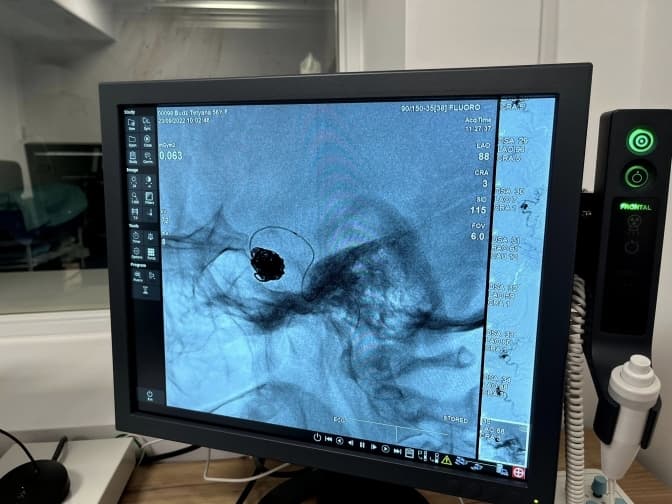

У лікарні Святого Луки медики врятували життя 56-річної пацієнтки з величезною аневризмою розміром у півтора сантиметра. Пацієнтка – мешканка Турківщини. Про це повідомили у Першому ТМО Львова.

Після діагностики жінці повідомили: у неї велика аневризма мозкової артерії. А наступного дня спеціалісти відділення реперфузійної терапії та радіології виконали емболізацію – закриття аневризми з допомогою мозкових спіралей. Операція відбулась без розрізів – лише одним проколом довжиною до 5 мм.